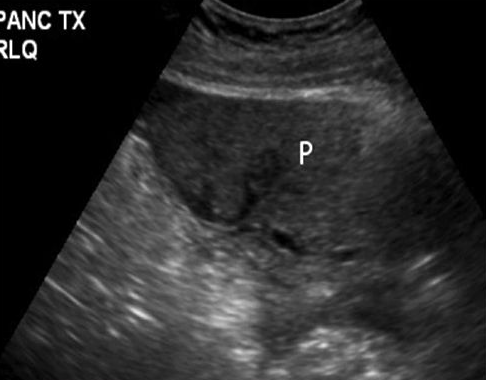

Describe this image

US guided FNA of a pancreatic tumor located in the head of the pancreas (based on landmarks)